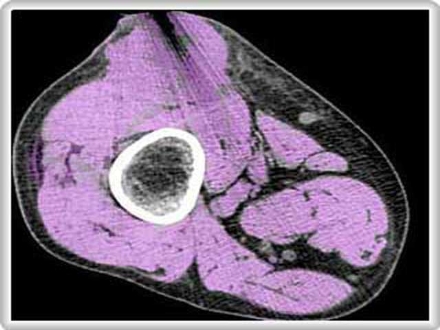

نانو ذرات پاسخ مناسبي براي دستيابي به اين هدف هستند. نانوذرات توليد شده توسط Cerulean براي خروج از رگهاي خوني و ورود به بافت سالم بسيار بزرگ هستند اما اندازه آنها براي ورود به تومورها به دليل وجود سوراخ و شكاف در رگهاي اطراف اين بافتها بسيار مناسب است.